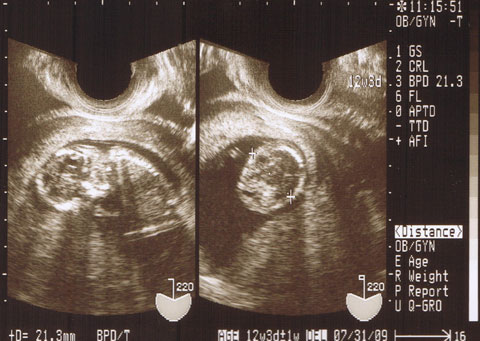

健診

今日は豆太郎に会ってきました!!

大きくなったね〜。ママ嬉しかったよ。

心臓もしっかり動いてるし、背骨も、腕も足も見えました。

宇宙人みたいだった1ヶ月前に比べると、

本当に人間らしくなりました。